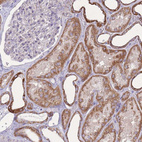

Immunohistochemical staining of human heart muscle shows strong cytoplasm granular positivity in cardiomyocytes.